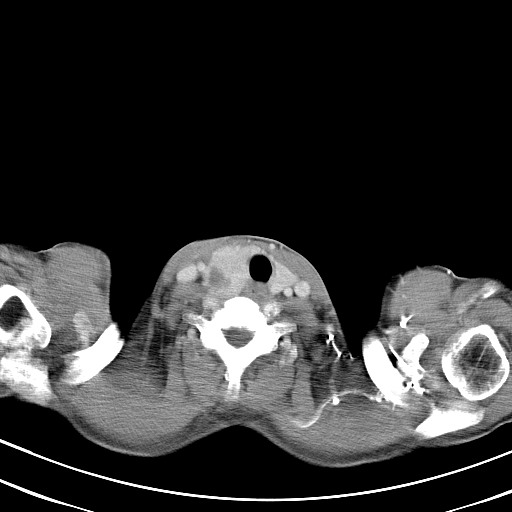

以下是引用汪涛同志在2007-8-2 0:40:00的发言:[br]病变虽然广泛,同时侵及双侧纵隔,但是无论左侧和右侧上下观察都是与右侧颈部甲状腺相延续的,而且强化幅度基本一致,又同时具有恶性病变病变的某些特征:肿块过大且密度不均,部分层面与正常纵隔结构分界不清,结合病史已有两年,考虑:胸内甲状腺肿恶变可能。[br]